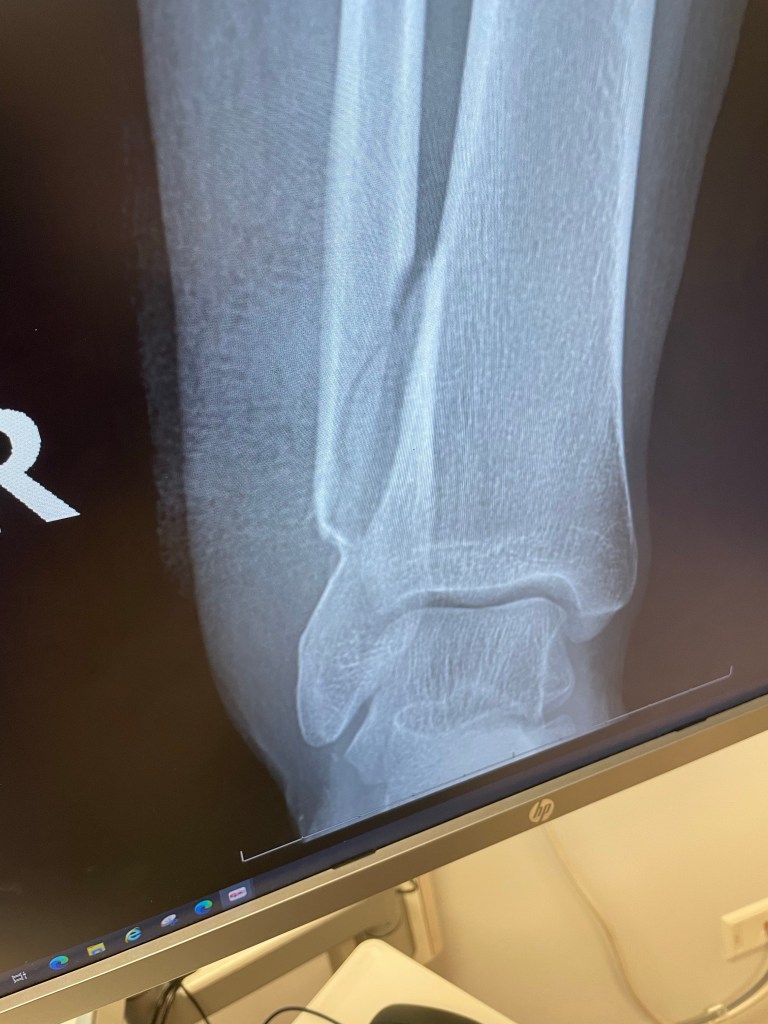

Steve relayed that he didn’t think Camy’s leg was broken, and if it was it was likely a minor fracture. He showed us her shoe which was covered in blood and told us that the blood just never stopped coming out of the wound the whole way to the hospital. News developed quickly and we learned that Camy had a significant open fracture to her Fibula, that she may need emergency surgery, and that this injury was quite serious. Steve ended up driving Camy to a hospital in Modesto, her surgery got pushed back, and Camy and Perry wound up on a flight from Oakland to Denver the next morning. Steve returned to us the next day and we then began the talks of whether or not to continue the mission without Camryn and Perry.